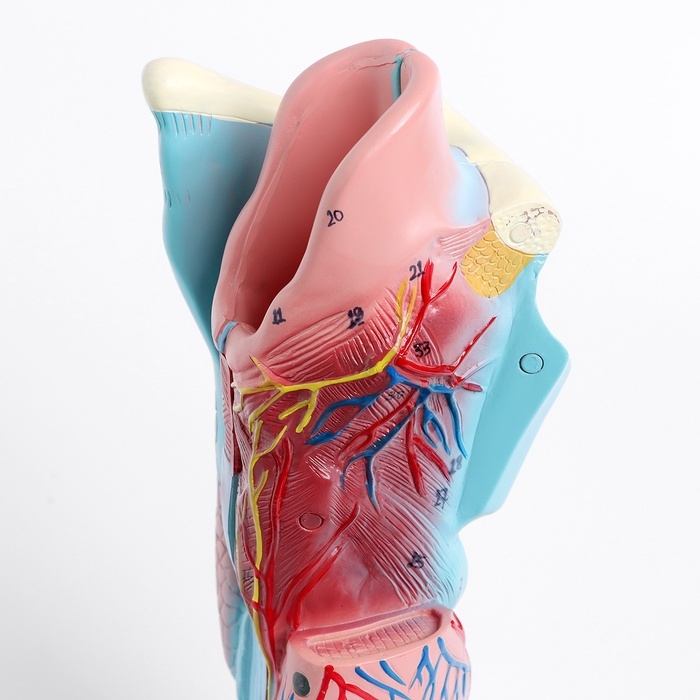

ЕКБ 39

No Brand, артикул: 7072361